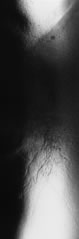

Other stains should be used if a fluorescent microscope is not available. The Gram stain does not stain the cell wall or septa of hyphal fragments but is absorbed by the protoplasm. The stain characteristics are inconsistent and nonspecific (Fig. 24). Yeasts typically stain dark blue and can be readily distinguished from bacteria, foreign material, precipitate, and other artifacts. The Giemsa stain is a simple, rapid method for identifying fungal elements, although not as sensitive as acridine orange or calcofluor white in detecting hyphal fragments and yeasts. The Giemsa stain has an affinity for DNA and ribonucleic acid (RNA) in microorganisms. The stain must be prepared fresh daily according to standards. The preferred method is to fix the smear in 95% methanol for 5 to 10 minutes, immerse the slide in Giemsa stain for 1 hour, rinse the slide briefly in 95% ethanol, blot dry, and examine by standard light microscopy. Hyphal fragments and yeasts appear dark blue or purple.

Fig. 24. F. solani keratitis. Light microscopy. Gram stain of direct smear of corneal scraping. Note the deposition of stain within the background material and channels of the hyphal fragments. (× 400.)